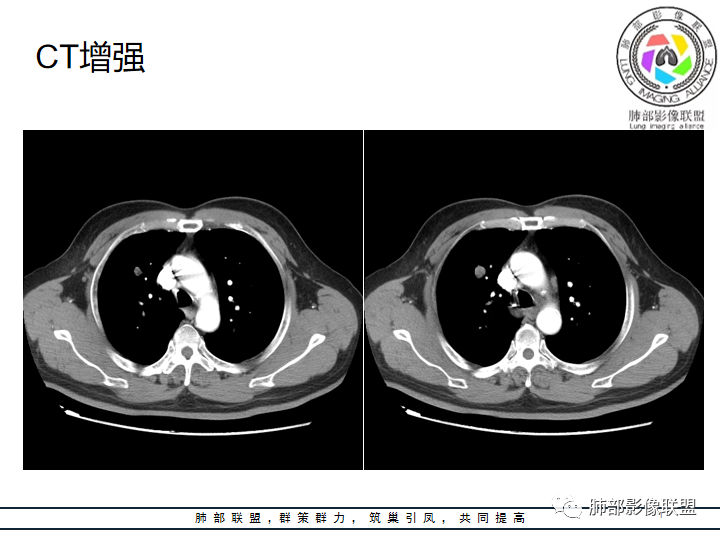

老年男性患者,长期吸烟史,没有呼吸系统临床表现。胸部CT示右肺上叶实性密度结节影,密度均匀,未见空洞及钙化,边缘较光整,未见分叶及毛刺。血管影旁现侧出,支气管进入并截断,不均匀强化。

赵国千:男性62岁,右肺上叶前段见结节,可见支气管穿行其中,增强轻度强化,倾向良性肿瘤,首先错构瘤、腺瘤;恶性肿瘤,淋巴瘤、淋巴上皮瘤样癌,这个比较难。

冯连彩:老年男性,有吸烟史,因腹疼入院查体发现肺部结节,右肺上叶前段结节,边缘光滑,浅分叶?支气管进入后截断,血管贴边,密度较高,有强化,考虑PSP或炎性假瘤?鉴别淋巴瘤,类癌?

蔡磊:右肺上叶实性结节,膨隆,收缩力弱,支气管近端有渐进性变窄,中等以上幅度强化,考虑神经内分泌癌,大?